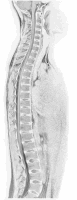

Campania este axata pe examenul clinic pentru depistarea tulburarilor de statica vertebrala: scolioza vertebrala, hipercifoza dorsala si hiperlordoza lombara si a dismorfismelor decelabile clinic (spondilolistezis).

Website: https://pansportmedical.ro/scolioza-cifoza-lordoza.html